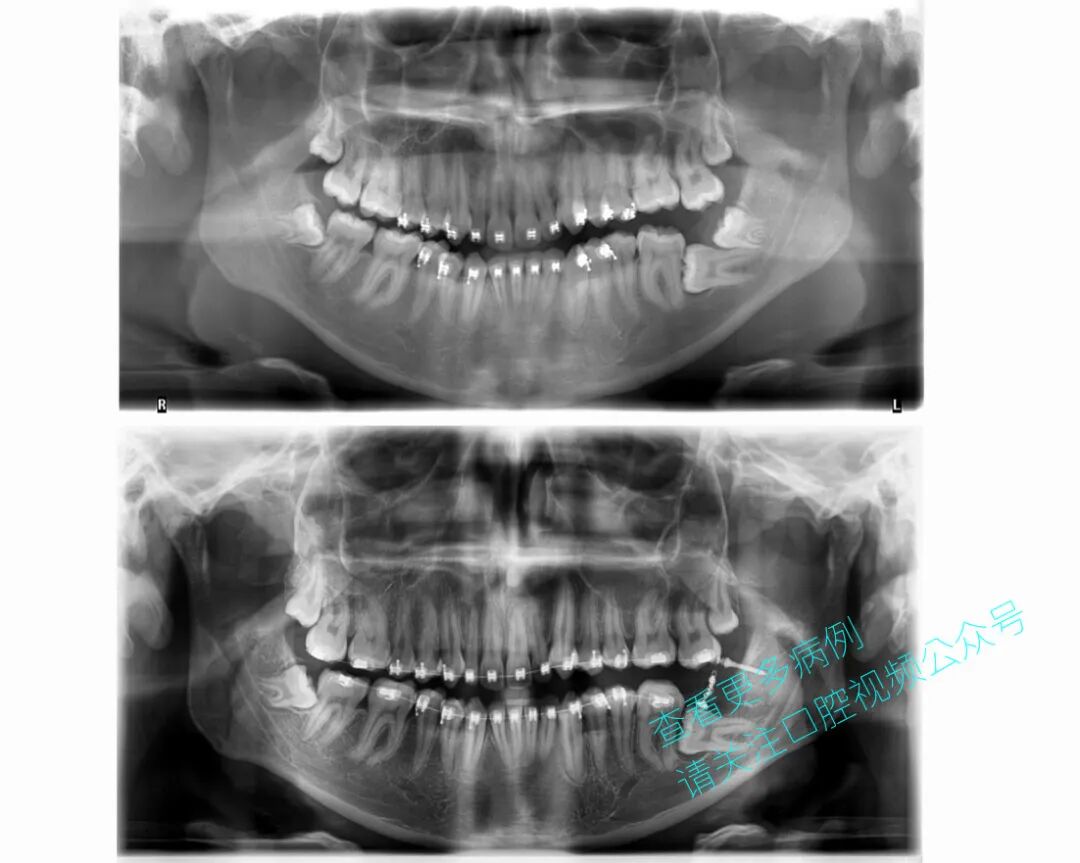

患者为18岁男性,既往接受过正畸治疗。37号牙水平阻生,紧贴36号牙。

该病例虽复杂,但取得了良好效果,成功避免了在青少年患者中植入种植体。